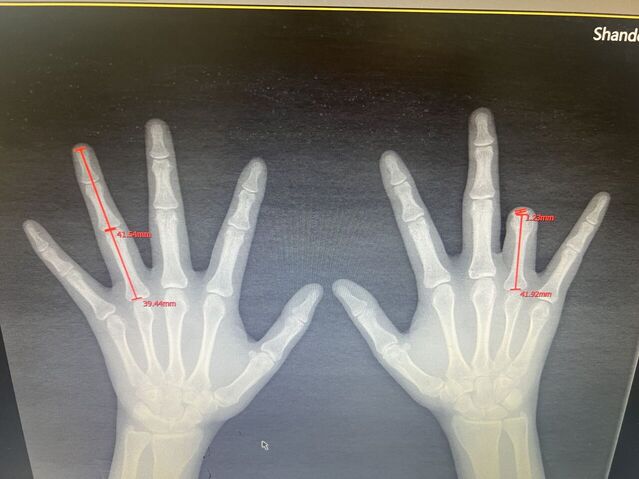

拇指再造术后一年半随访

微信图片_20231022194348.jpg 微信图片_20231022194355.jpg 微信图片_20231022194352.jpg 微信图片_20231022194345.jpg 微信图片_20231022194325.jpg 微信图片_20231022194333.jpg 微信图片_20231022194311.jpg 微信图片_20231022194245.jpg 微信图片_20231022194301.jpg 微信图片_20231022194254.jpg 微信图片_20231022193210.jpg 微信图片_20231022193225.jpg 微信图片_20231022193246.jpg 微信图片_20231022193237.jpg 微信图片_20231022194226.jpg 微信图片_20231022194231.jpg